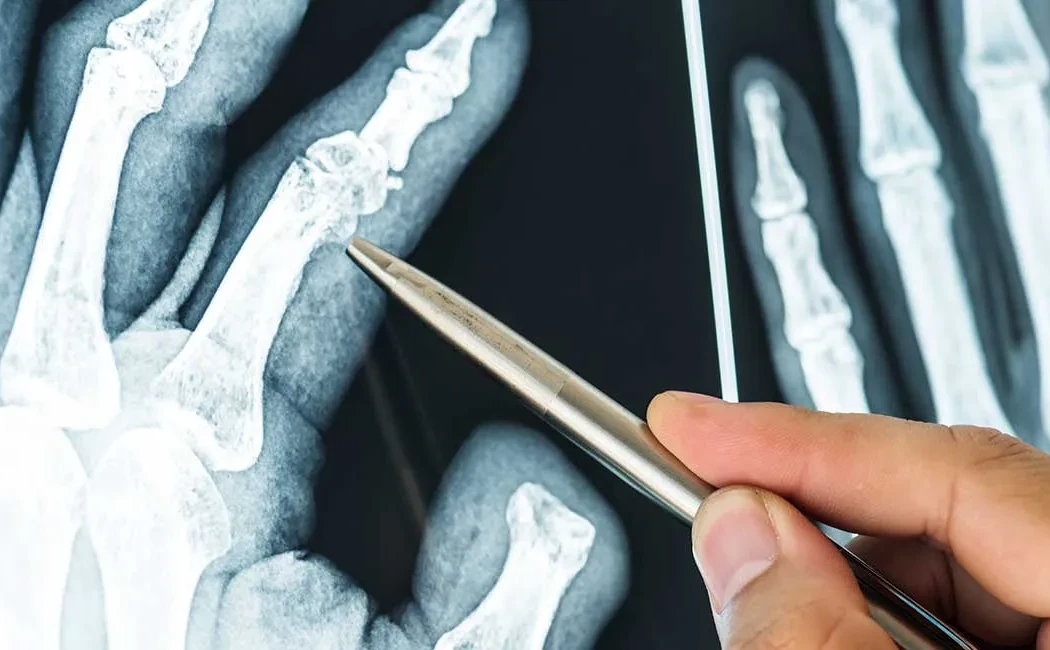

Kaynamama tanısı, detaylı bir fizik muayene ve ileri görüntüleme yöntemleri ile konulur. Hastalar genellikle kırık bölgesinde devam eden ağrı, patolojik hareketlilik ve yük verememe şikayetleri ile başvururlar. Tanı sürecinde ilk adım standart röntgen grafileridir; bu grafilerde kırık hattının kapanmadığı, implant yetmezliği veya kemik uçlarında skleroz görülebilir.

Daha detaylı değerlendirme için Bilgisayarlı Tomografi (BT) kullanılır. BT, kemik yapısını üç boyutlu olarak göstererek kaynamama tipinin (atrofik, oligotrofik, hipertrofik) belirlenmesine yardımcı olur. Enfeksiyon şüphesi varlığında ise Manyetik Rezonans Görüntüleme (MRG) ve laboratuvar testleri (CRP, Sedimantasyon, Lökosit) devreye girer. Sintigrafi veya lökosit işaretli görüntüleme yöntemleri, özellikle gizli enfeksiyonların ayırt edilmesinde önemli rol oynar.